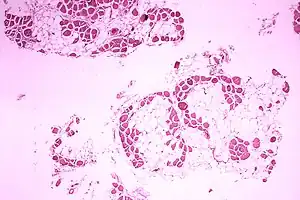

| Microscopic image of cross-sectional calf muscle from a person with Duchenne muscular dystrophy, showing extensive replacement of muscle fibers by fat cells. | |

DMD causes progressive muscle weakness due to muscle fiber disarray, death, and replacement with connective tissue or fat.[3] The voluntary muscles are affected first, especially those of the hips, pelvic area, thighs, calves.[10][11] It eventually progresses to the shoulders and neck, followed by arms, respiratory muscles, and other areas.[11] Fatigue is common.[12]